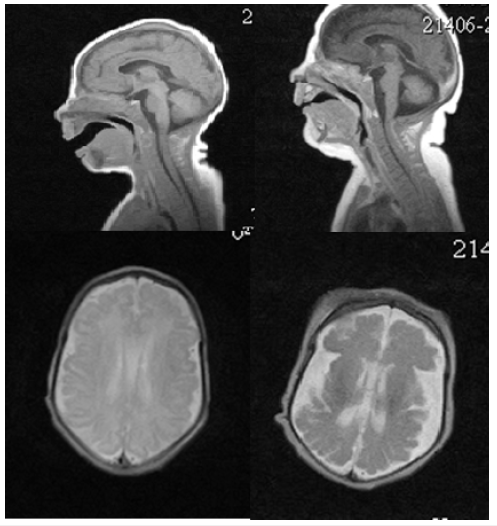

His neurologic examination demonstrated diffuse hypotonia with hyporeflexia, divergent strabismus, facial masking. At the age of 21 days of life, MRI was studied and found to have abnormalities of the cerebral cortex characterized the simplified gyral pattern (Figure 4). When re-MRI was studied at the age of 2 months, microgyria in the sylvian region on both sides and diffuse atrophic changes in the cerebral hemispheres and cerebellum were assessed (Figure 4).

In the first of study we sought to evaluate the decreased myelination in the posterior limb of the internal capsule as the physiological (G). From the age of 2 months, decreased myelination assessed as pathological (Figure 5). Bone age assessment of the wrist was performed at the age of 4 months, ossification centers in carpal bones were not not have been detected. At the age of 4 months, a genetic examination carried out, a previously undescribed variant of the nucleotide sequence was diagnosed in exon 2 of the STAMBP gene chr2: 74058171rs781694797 188A> G in the homozygous state, resulting in the replacement of the amino acid p.Tyr63Cys in 63 position of the protein. This type of mutation was also detected in the father and mother in the heterozygous state. This variant is considered as pathogenic, related to the patient’s phenotype.

Figure 4:MRI of the brain M.R. at the 21 days of life (A, C) and 2 months of life (B, D). A, C the pattern of “microcephaly with simplified gyral pattern». Polymicrogyria in the sylvian fissure region shown by the arrow (D).

Figure 5:MRI of the brain of a boy M.R. at the age of 21 days (A) and 2 months (B). Signal changes in the PLIC are visually evaluated on FLAIR images is indicated by an arrow.